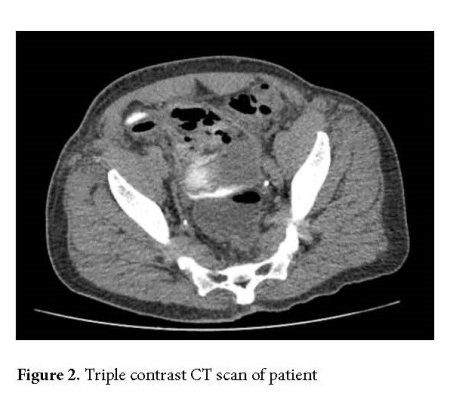

On postoperative day 41, the patient returned to the emergency department with symptoms of fatigue, dysuria, and foul-smelling urine. A CT scan with intravenous, rectal, and oral contrast was performed, raising suspicion for an enterovesical fistula (Fig. 2). The patient was subsequently taken to the operating room for cystoscopy and cystography, which revealed necrosis of the right lateral bladder wall and dome, along with the presence of an extraperitoneal fistula.